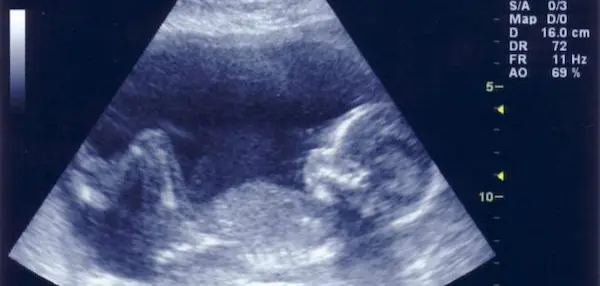

- الموجات فوق الصوتية

إذا كنتِ تبحثين عن إجابة سؤال متى يظهر نوع الجنين؟ فمن الممكن أن يجيب عليكِ فحص الموجات فوق الصوتية، والذي يعد فحص روتيني قبل الولادة، ويساهم في تكوين صورة لجنينكِ؛ للتحقق من نموه، وصحته.

ويمكنكِ معرفة نوع الجنين عن طريق الخضوع لذلك الفحص الذي يجرى عادةً بين الأسبوعين 18، و22، حيث يتمكن الطبيب من النظر إلى أعضائه التناسلية.

لذا قد يساعدكِ مركز صحة المرأة بمستشفى الموسى التخصصي على معرفة نوع الجنين بدقة، وذلك لتوفر أحدث أجهزة الموجات فوق الصوتية. كما أنه سيساعدكِ على مراقبة الآتي